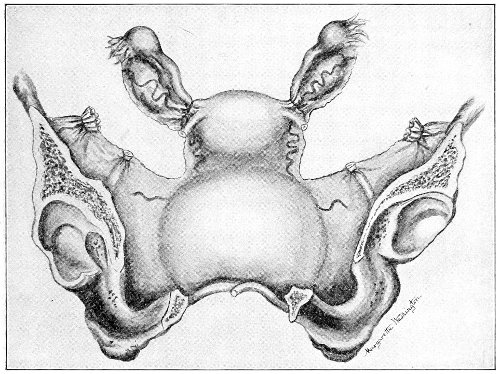

An accurate knowledge of the anatomy and mechanism of the female perineum is essential to an understanding of the nature and treatment of injuries to this structure. The anatomical structures lying between the anus behind and the symphysis pubis in front are those that most directly interest the gynecologist. Proceeding from 57 below upward, we find the following structures lying in superimposed planes: the skin, the superficial fascia, the deep layer of the superficial fascia, the transversus perinæi and the sphincter vaginæ muscles, the anterior layer of the triangular ligament, the posterior layer of the triangular ligament, the levator ani muscle (Fig. 19).

The vagina passes through these structures. They surround and support the ostium vaginæ as the fascia and muscles surround and support the opening of the rectum or the anus. The muscles and fasciæ are attached in the median line between the anus and the vagina, and therefore this part of the body, which is called the perineum, is supported or maintained in its 58 proper position by these various structures. The transversus perinæi arises from the ramus of the ischium and is inserted in the perineum. The bulbo-cavernosus, or sphincter vaginæ, arises in the perineum and is inserted in and about the clitoris. The inner fibers of the levator ani arise from the symphysis pubis and are inserted in the perineum and the lower part of the vagina (Fig. 20). When these muscles contract, their action, therefore, is to draw the perineum upward and forward. At the same time the anus is drawn upward and forward, and so also is the posterior margin of the ostium vaginæ and the lower portion of the posterior vaginal wall.

The vagina has no circular sphincter like the anus, but 59 the vaginal month is kept closed by the action of the transversus perinæi, sphincter vaginæ, and levator ani muscles, which draw the perineum forward, and thus keep the posterior vaginal wall in apposition with the anterior wall.

Fig. 21.—Muscular floor of the pelvis seen from above.

This sling of muscles and fascia, which surrounds and supports the opening of the vagina, may readily be felt in the nulliparous woman by introducing the finger in the vagina and pressing backward and outward toward the ischio-rectal fossa. We then feel plainly, immediately within the ostium vaginæ, a firm resisting band of tissue, apparently about half an inch broad, embracing the posterior portion of the lower vagina. This band is formed by the inner edges of the various muscles and planes of fascia that have been described.

The vagina extends, as a transverse slit in the pelvic floor, upward and backward, approximately in the direction 60 of a line drawn from the ostium vaginæ to the fifth sacral vertebra. It is approximately parallel with the conjugate of the brim, so that when the woman is erect the long axis of the vagina is inclined at an angle of 60° to the horizon. The vagina is not a vertical open tube: it is a slit in the pelvic floor, in health always closed by the accurate apposition of the anterior and posterior walls (Fig. 21). The anterior vaginal wall is about 2½ inches long in a vertical mesial line. The posterior vaginal wall is about 3½ inches long. The vaginal walls are triangular in shape, being broader above than below. The shape of the normal vagina at the pelvic outlet is shown by Fig. 23. The section here shows the vaginal 61 slit of the shape of the letter H. The portions of the slit extending backward and somewhat outward are called the vaginal sulci or furrows. They are directions of diminished resistance in which tears are liable to occur.